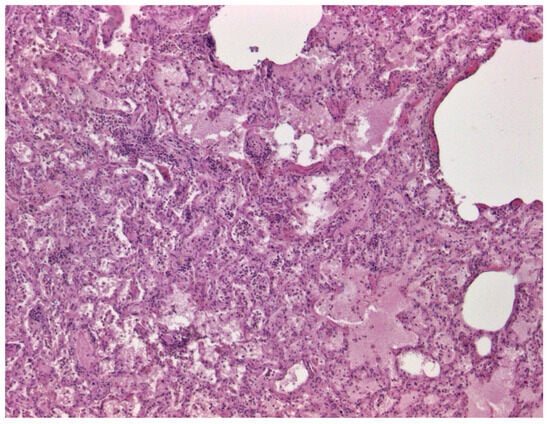

3.1. Necropsy and Histopathology Data